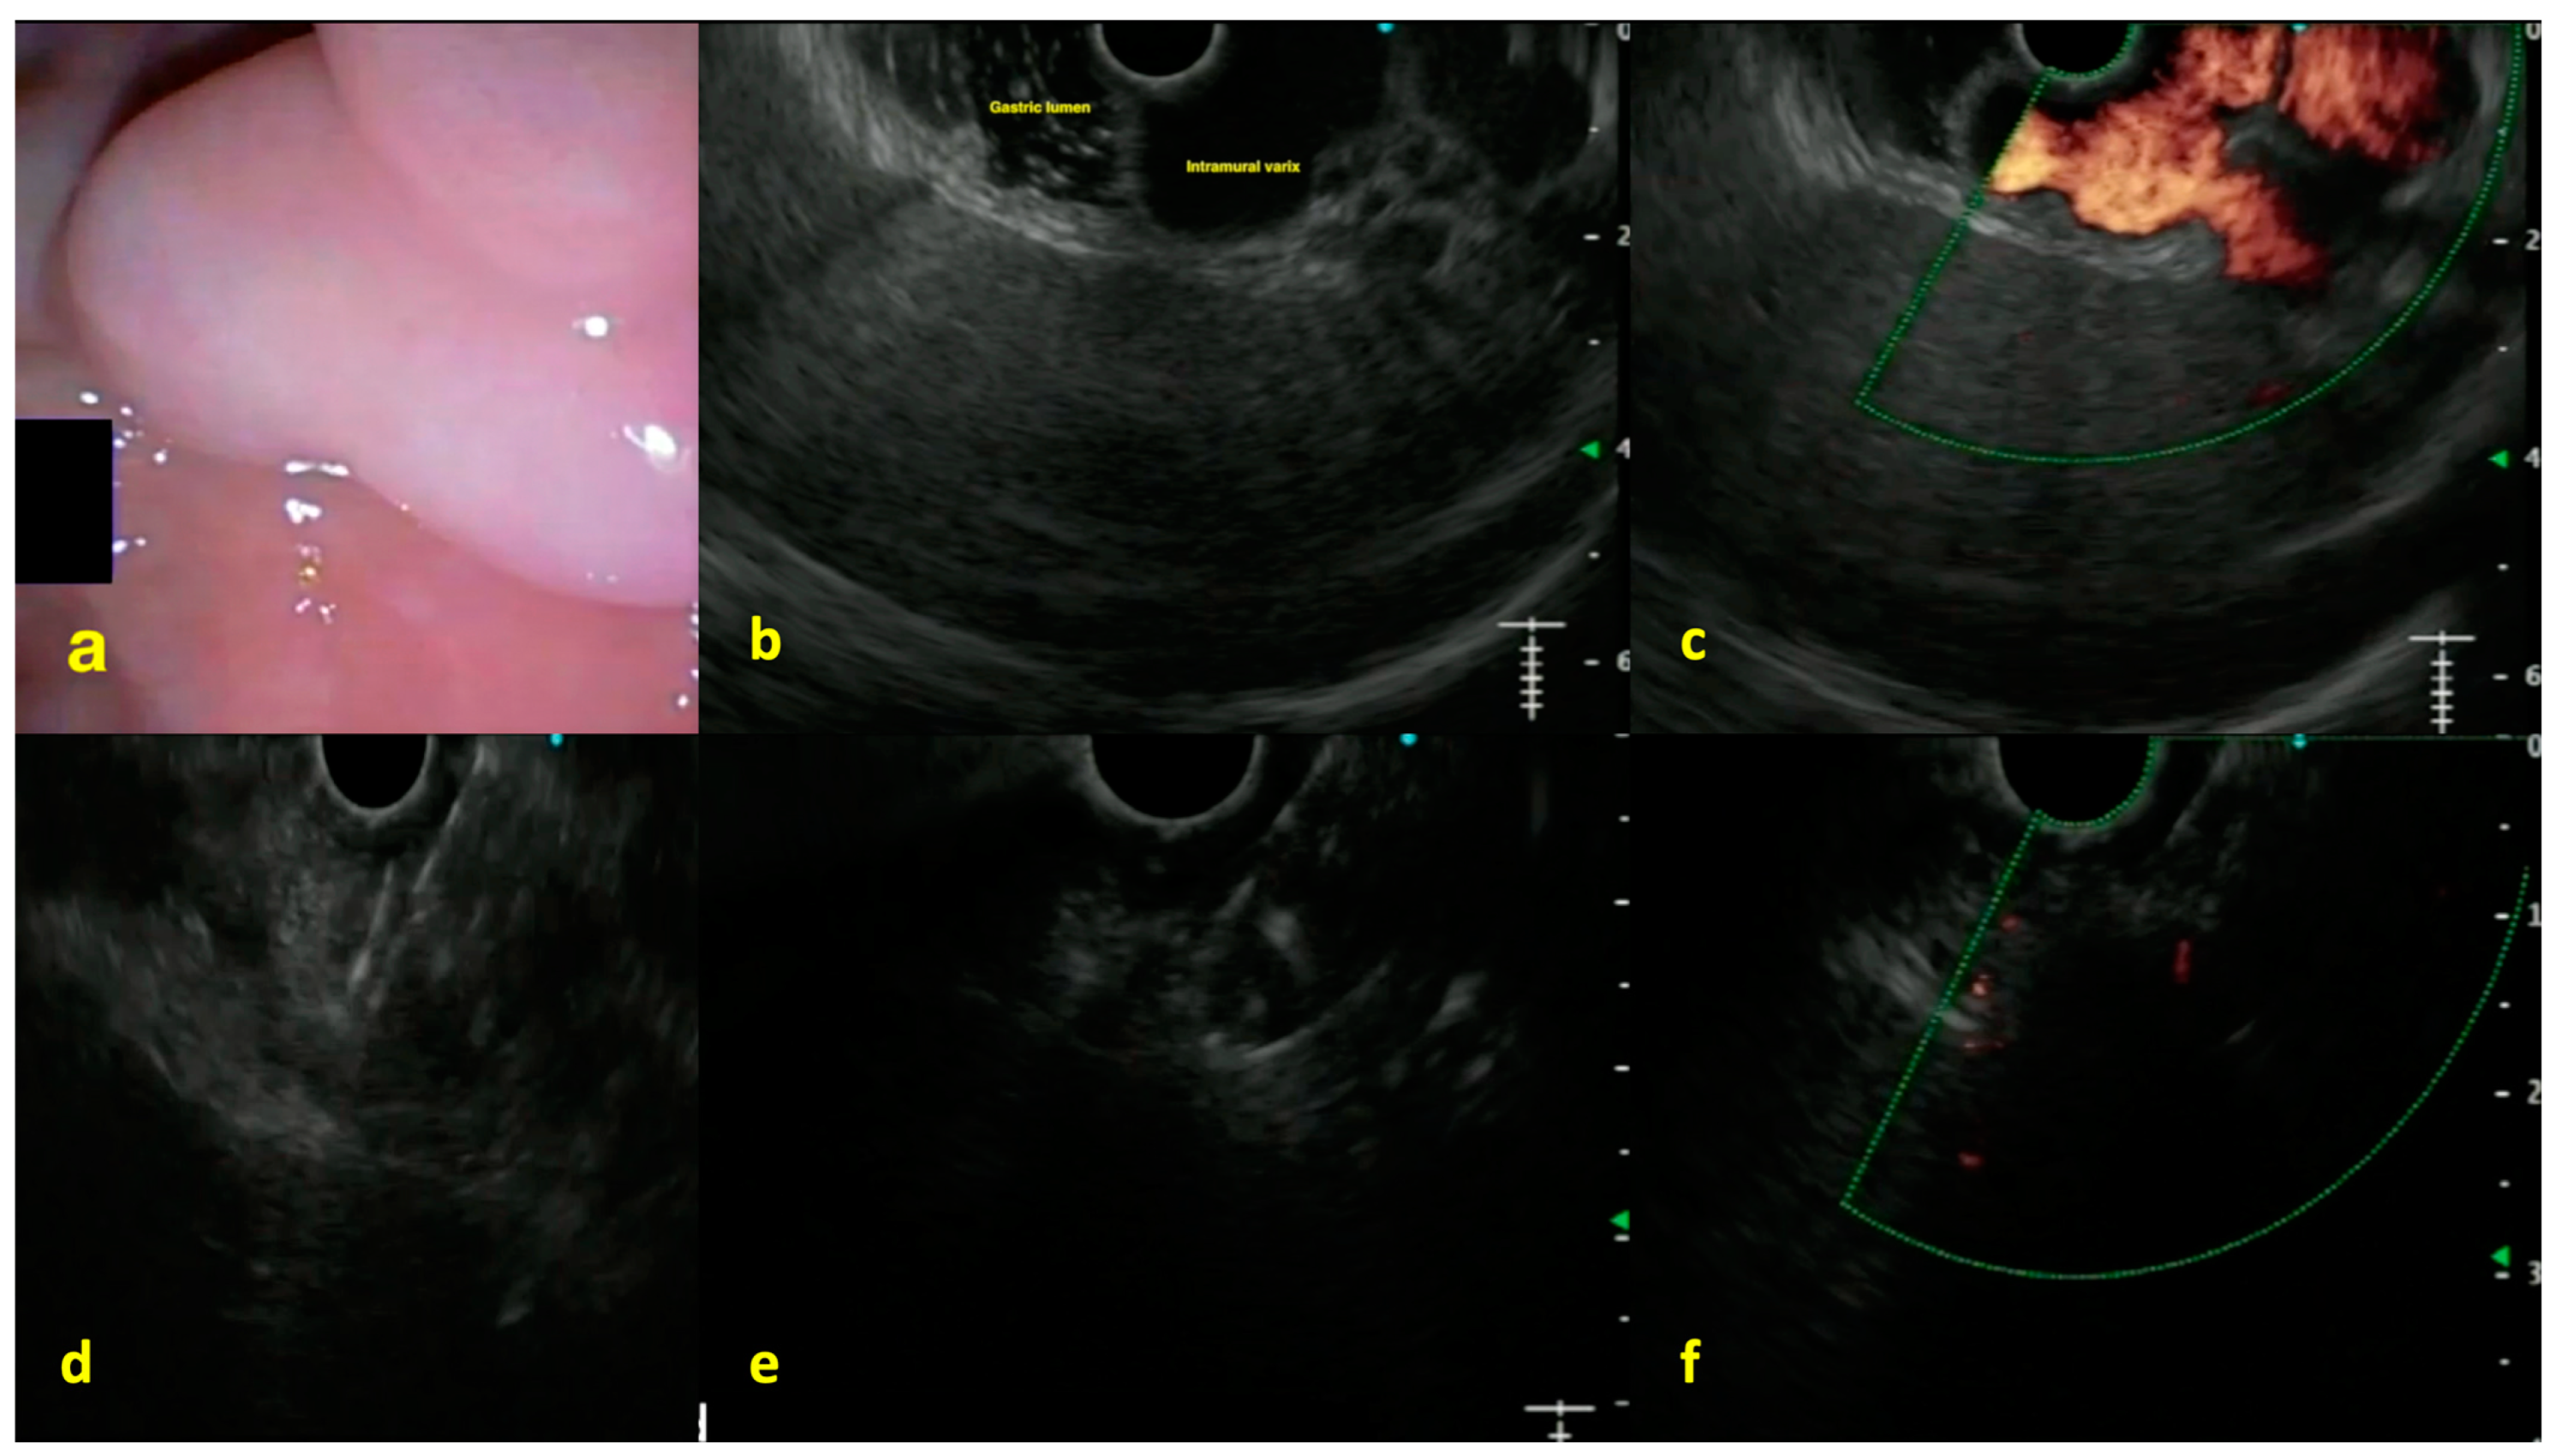

- Florencio de Mesquita, C.; Antunes VL, J.; Milioli, N.J.; Fernandes, M.V.; Correa, T.L.; Martins, O.C.; Chavan, R.; Baraldo, S. EUS-guided coiling plus glue injection compared with endoscopic glue injection alone in endoscopic treatment for gastric varices: A systematic review and meta-analysis. Gastrointest. Endosc. 2024, 101, 331–340.e8. [Google Scholar] [CrossRef]

- Manolakis, A.; Tsagkidou, K.; Koumarelas, K.E. Endoscopic ultrasound-guided therapies in the treatment of gastric varices: An in-depth examination of associated adverse events. World J. Gastrointest. Endosc. 2024, 16, 640. [Google Scholar] [CrossRef] [PubMed]

- Binmoeller, K.F.; Weilert, F.; Shah, J.N.; Kim, J. EUS-guided transesophageal treatment of gastric fundal varices with combined coiling and cyanoacrylate glue injection (with videos). Gastrointest. Endosc. 2011, 74, 1019–1025. [Google Scholar] [CrossRef]

- Mohan, B.P.; Chandan, S.; Khan, S.R.; Kassab, L.L.; Trakroo, S.; Ponnada, S.; Asokkumar, R.; Adler, D.G. Efficacy and safety of endoscopic ultrasound-guided therapy versus direct endoscopic glue injection therapy for gastric varices: Systematic review and meta-analysis. Endoscopy 2020, 52, 259–267. [Google Scholar] [CrossRef]

- Samanta, J.; Nabi, Z.; Facciorusso, A.; Dhar, J.; Akbar, W.; Das, A.; Birda, C.L.; Mangiavillano, B.; Auriemma, F.; Crino, S.F.; et al. EUS-guided coil and glue injection versus endoscopic glue injection for gastric varices: International multicentre propensity-matched analysis. Liver Int. 2023, 43, 1783–1792. [Google Scholar] [CrossRef]